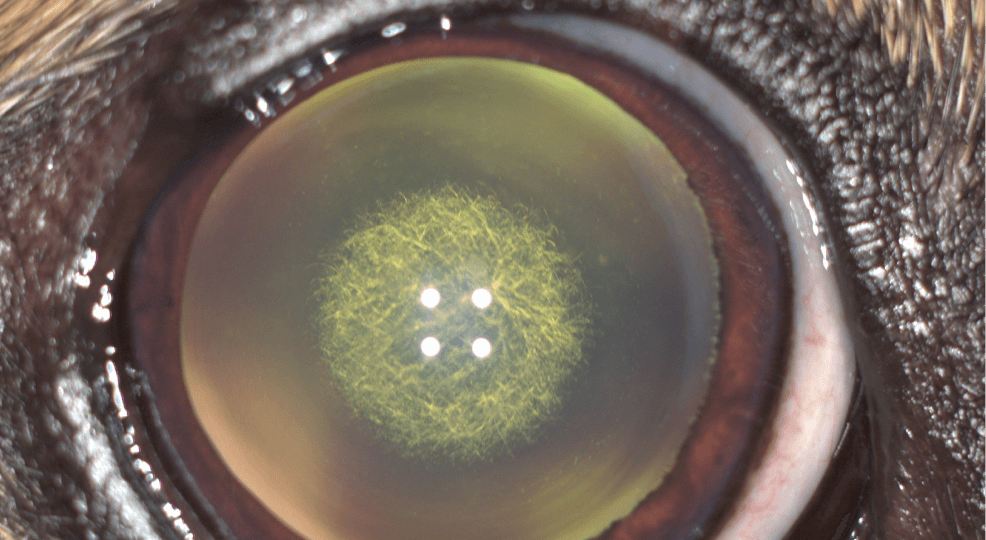

Владельцы могут заметить у собаки подозрительное помутнение или белесые пятна на фоне черного зрачка. Однако это необязательно говорит о катаракте. Так могут проявляться, например, повреждение роговицы или помутнение жидкости в передней камере глаза. Если все-таки именно хрусталик потерял свою прозрачность, стоит исключить такое похожее заболевание, как ядерный склерозЭто возрастное изменение, при котором увеличивается плотность ядра хрусталика. Обычно ядерный склероз появляется у собак старше 7 лет и может развиваться вместе с катарактой.. Отличить эти патологии друг от друга и поставить точный диагноз может только врач-офтальмолог по результатам комплексного обследования.

1. Без катаракты

2. Со зрелой катарактой

3. С начальной катарактой и ядерным склерозом

Также различают четыре стадии заболевания: врач оценивает степень повреждения хрусталика и нарушения зрения, светоотражающее свойство тапетума («зеркала» на глазном дне), наличие сопутствующих патологий. По данным критериям болезнь бывает начальной, незрелой, зрелой и перезрелой.